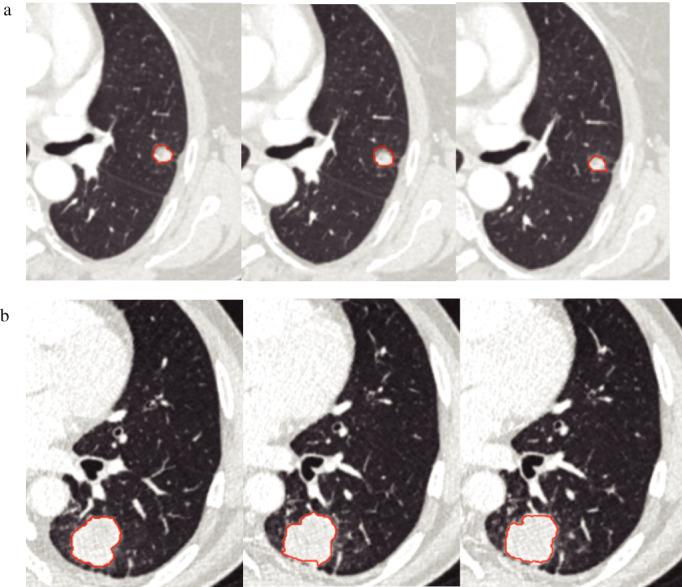

Different CT slice thickness and contrast-enhancement phase in radiomics models on the differential performance of lung adenocarcinoma.

To investigate the effects of computed tomography (CT) reconstruction slice thickness and contrast-enhancement phase on the differential diagnosis performance of radiomic signature in lung adenocarcinoma.

A total of 187 patients who had been pathologically confirmed with lung adenocarcinoma and nonadenocarcinoma were divided into a training cohort (n = 149) and validation cohort (n = 38). All the patients underwent contrast-enhanced CT and the images were reconstructed with different slice thickness. The radiomic features were extracted from different slice thickness and scan phase. The logistic regression (LR) algorithm was used to build a machine learning model for each group. The area under the curve (AUC) obtained from the receiver operating characteristic (ROC) curve and DeLong test was used to evaluate its discriminating performance.

Finally, 34 image features and five semantic features were selected to establish a radiomics model. Based on the three contrast-enhanced CT phases and four reconstruction slice thickness, 12 groups of radiomics models showed good discrimination ability with the AUCs range from 0.9287 to 0.9631, sensitivity range from 0.8349 to 0.9083, specificity range from 0.825 to 0.925 in the training group. Similar results were observed in the validation group. However, there was no statistical significance between the different CT scan phase groups and different slice thickness (p > 0.05).

The radiomic analysis of contrast-enhanced CT can be used for the differential diagnosis of lung adenocarcinoma. Moreover, different slice thickness and contrast-enhanced scan phase did not affect the discriminating ability in the radiomics models.